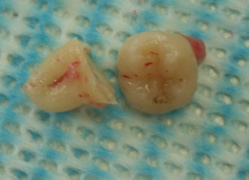

10代後半の男性です。根は多少広がっていますが、比較的簡単な抜歯と判断しました。(上下の親知らずを一度に抜歯しました)

抜いた下の親知らずです。麻酔後、抜歯に取りかかってから終了まで上下で2分ほどで終了してます。